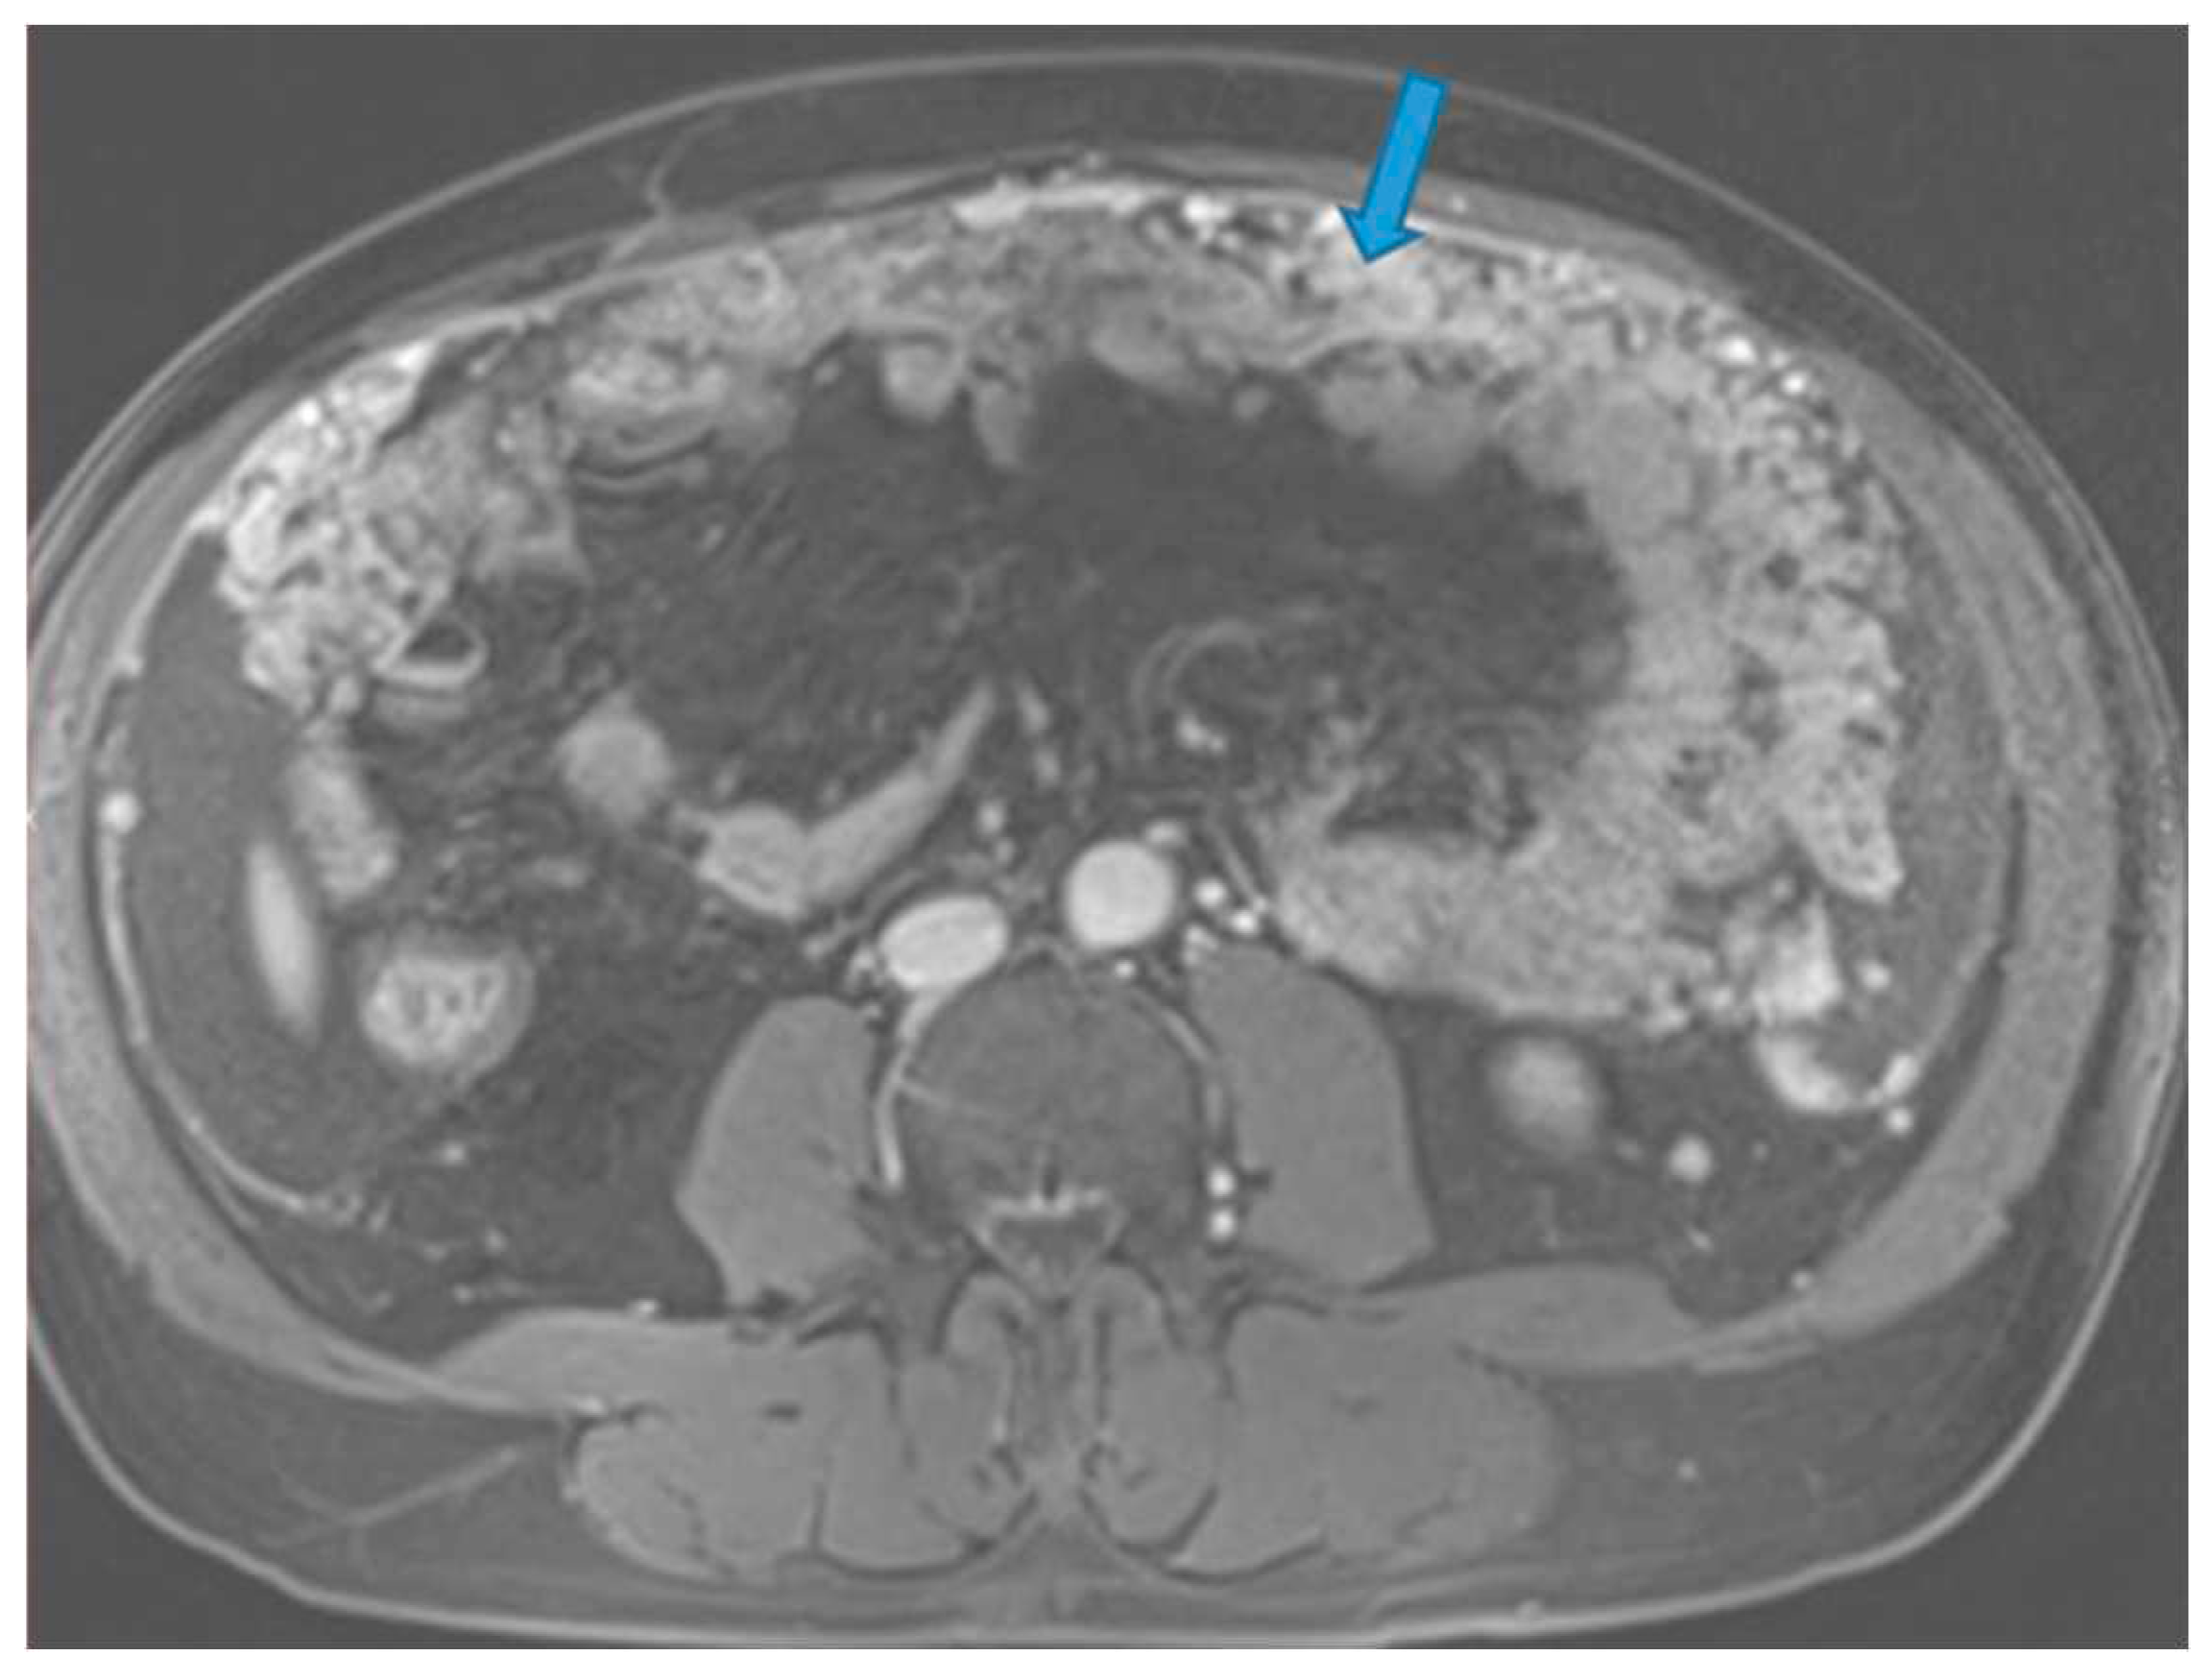

Figure 26.

Axial CE-CT (A). PC from stomach adenocarcinoma: Stellate mesentery. Axial CE portal phase FST1WI (B). PC from lobular breast adenocarcinoma: Stellate mesentery, notice the perivascular distribution. Axial CE-CT (C), axial T2WI (D). PC from stomach adenocarcinoma: Isolated perivascular deposit within the mesentery, as a soft tissue mass surrounding a branch of the SMV.